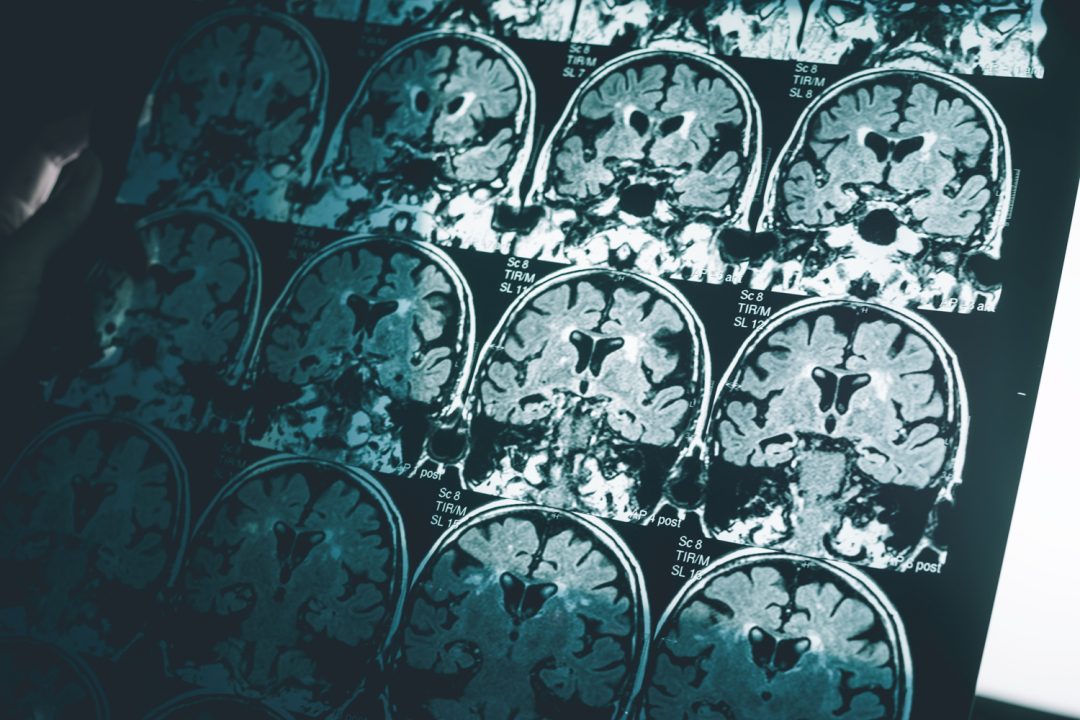

Researchers from Kaunas universities, Lithuania developed a deep learning-based method that can predict the possible onset of Alzheimer’s disease from brain images with an accuracy of over 99 per cent. The method was developed while analysing functional MRI images obtained from 138 subjects and performed better in terms of accuracy, sensitivity and specificity than previously developed methods.

One of the possible Alzheimer’s first signs is mild cognitive impairment (MCI), which is the stage between the expected cognitive decline of normal ageing and dementia. Based on the previous research, functional magnetic resonance imaging (fMRI) can be used to identify the regions in the brain which can be associated with the onset of Alzheimer’s disease, according to Maskeli?nas. The earliest stages of MCI often have almost no clear symptoms, but in quite a few cases can be detected by neuroimaging.

The deep learning-based model was developed as a fruitful collaboration of leading Lithuanian researchers in the Artificial Intelligence sector, using a modification of well-known fine-tuned ResNet 18 (residual neural network) to classify functional MRI images obtained from 138 subjects. The images fell into six different categories: from healthy through the spectre of mild cognitive impairment (MCI) to Alzheimer’s disease. In total, 51,443 and 27,310 images from The Alzheimer’s Disease Neuroimaging Initiative fMRI dataset were selected for training and validation.

The model was able to effectively find the MCI features in the given dataset, achieving the best classification accuracy of 99.99%, 99.95%, and 99.95% for early MCI vs. AD, late MCI vs. AD, and MCI vs. early MCI, respectively.